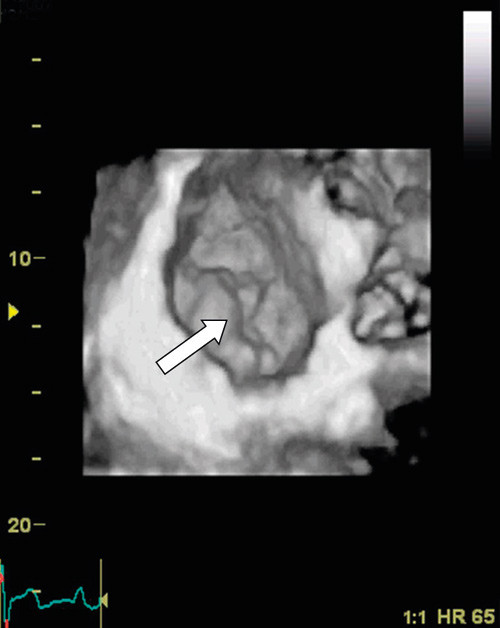

Using 3D echocardiography with full volume recording, the left ventricle can be represented as multiple short-axis images on the screen (Figure 4). In heart muscle diseases such as hypertrophic cardiomyopathy, a better overview can be obtained of where the hypertrophy is distributed. This is particularly useful with more apical variants, as they can be overlooked in routine echocardiography. Some rarer forms of cardiomyopathy, such as non-compaction cardiomyopathy, have characteristic features which can be reproduced easily with 3D echocardiography (Figure 5). However, the additional value of 3D echocardiography in various cardiomyopathies has not as yet been well documented.

Figure 5  Short-axis section of left ventricle in patient with non-compaction cardiomyopathy. In apical sections «spongy»…

Figure 5 Short-axis section of left ventricle in patient with non-compaction cardiomyopathy. In apical sections «spongy» tissue can be observed with prominent crypt formation. In real-time imaging significantly impaired contractions of the ventricle can be seen.